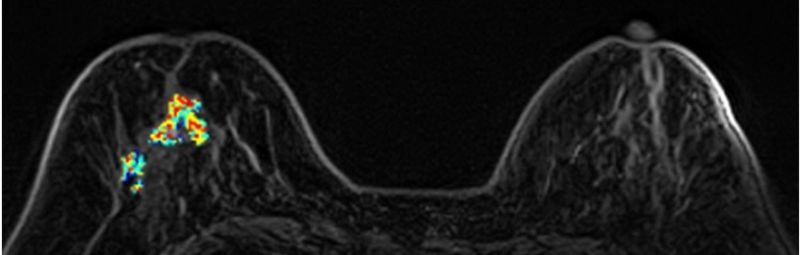

64歲石小姐,曾接受矽膠注射隆乳,因右乳疼痛求診,但矽膠在乳房攝影及超音波下會遮蔽病灶而無法診斷,經磁振造影MRI發現:右乳有一不規則腫塊(約55mm)、乳頭內縮,高度懷疑惡性腫瘤,經手術證實為乳癌。

(3)乳房MRI磁振造影檢查:

無輻射、高解析度、無痛的高階影像檢查,對偵測腫塊病灶有極高的敏感度,是極佳的診斷利器。適用有乳癌家族史、曾罹患卵巢癌及子宮內膜癌者、帶有特定家族遺傳基因(BRCA1、BRCA2等),或曾接受乳房手術的女性(如自體脂肪豐胸、假體植入、矽膠注射隆乳),建議至少每兩年一次MRI檢測,除偵測早期乳癌外,同時可評估植入物之完整性。